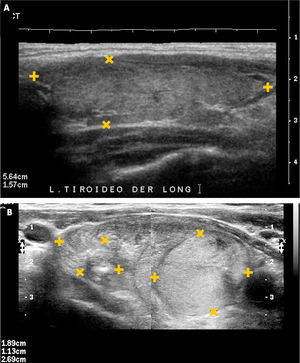

EL TIROIDES NORMAL Y PATOLÓGICOEl tiroides normal al ultrasonido tiene la forma de una letra H (para otros como mariposa), con lóbulos derecho e izquierdo con predominio franco del eje cráneo caudal, algunos más y otros menos estilizados, de contornos lisos, de bordes más bien agudos, generalmente entre 30 y 60mm de eje longitudinal según la literatura (entre 30 y 42mm en mi experiencia) (Figura 1). El istmo también con predominio del eje longitudinal, con un diámetro anteroposterior no mayor a

3mm (Figura 2). La presencia del lóbulo piramidal no es rara, alrededor del 20%11, siendo dependiente la mayoría de las veces del istmo y las otras veces del borde medial del lóbulo izquierdo (Figura 3).

La disminución de tamaño del tiroides, sin antecedentes de cirugía, frecuentemente se debe a procesos inflamatorios crónicos de larga data. Por otra parte, frecuente en nuestra población, está el aumento de tamaño del tiroides: bocio, que puede ser difuso o nodular (uni o multinodular), causa de consulta médica general y segunda causa de consulta endocrinológica (Figura 5a y 5b).

Bocio.

A: Tiroides en un corte longitudinal, de forma globulosa aumentado de tamaño, contornos suavemente lobulados, parénquima hipoecogénico, heterogéneo, sin imágenes de nódulos en su espesor.

B: Tiroides en un corte longitudinal, globuloso aumentado de tamaño, contornos lobulados, hipoecogénico, heterogéneo, con nódulos sólidos de diferente tamaño.